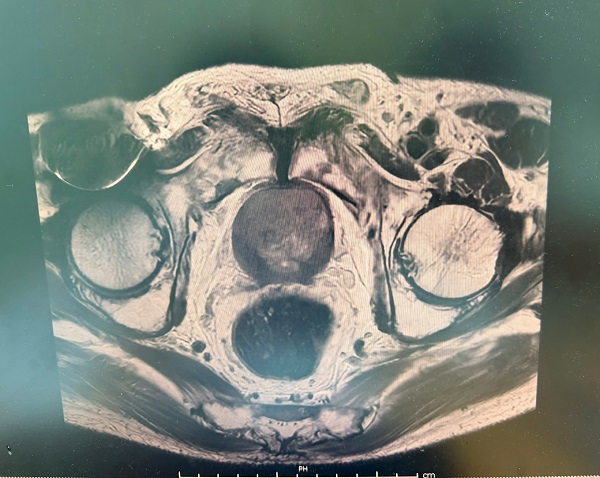

Thực hiện kĩ thuật chụp cộng hưởng từ chuyên sâu cho ung thư tiền liệt tuyến (mpMRI – multiparametric MRI) cho thấy, tuyến tiền liệt kích thước khoảng 49×46×37mm, thể tích tương đương ~43cm³. Tổn thương vùng ngoại vi phía sau lệch trái kích thước 9×12mm, bờ không đều. Tổn thương xâm lấn túi tinh cùng bên, chưa phát hiện xâm lấn cấu trúc lân cận khác. Từ đó, các bác sĩ đưa ra kết luận phân loại tổn thương PIRADS 5 - mức độ nghi ngờ ung thư rất cao.

Ngoài ra, hình ảnh cũng cho thấy có các nốt bất thường tín hiệu rải rác tại xương chậu hai bên và xương cùng, dấy lên khả năng di căn xương. Thoát vị bẹn trái kích thước khoảng 25×15mm gây áp lực ổ bụng, cũng là yếu tố cần được xem xét trong quá trình điều trị.